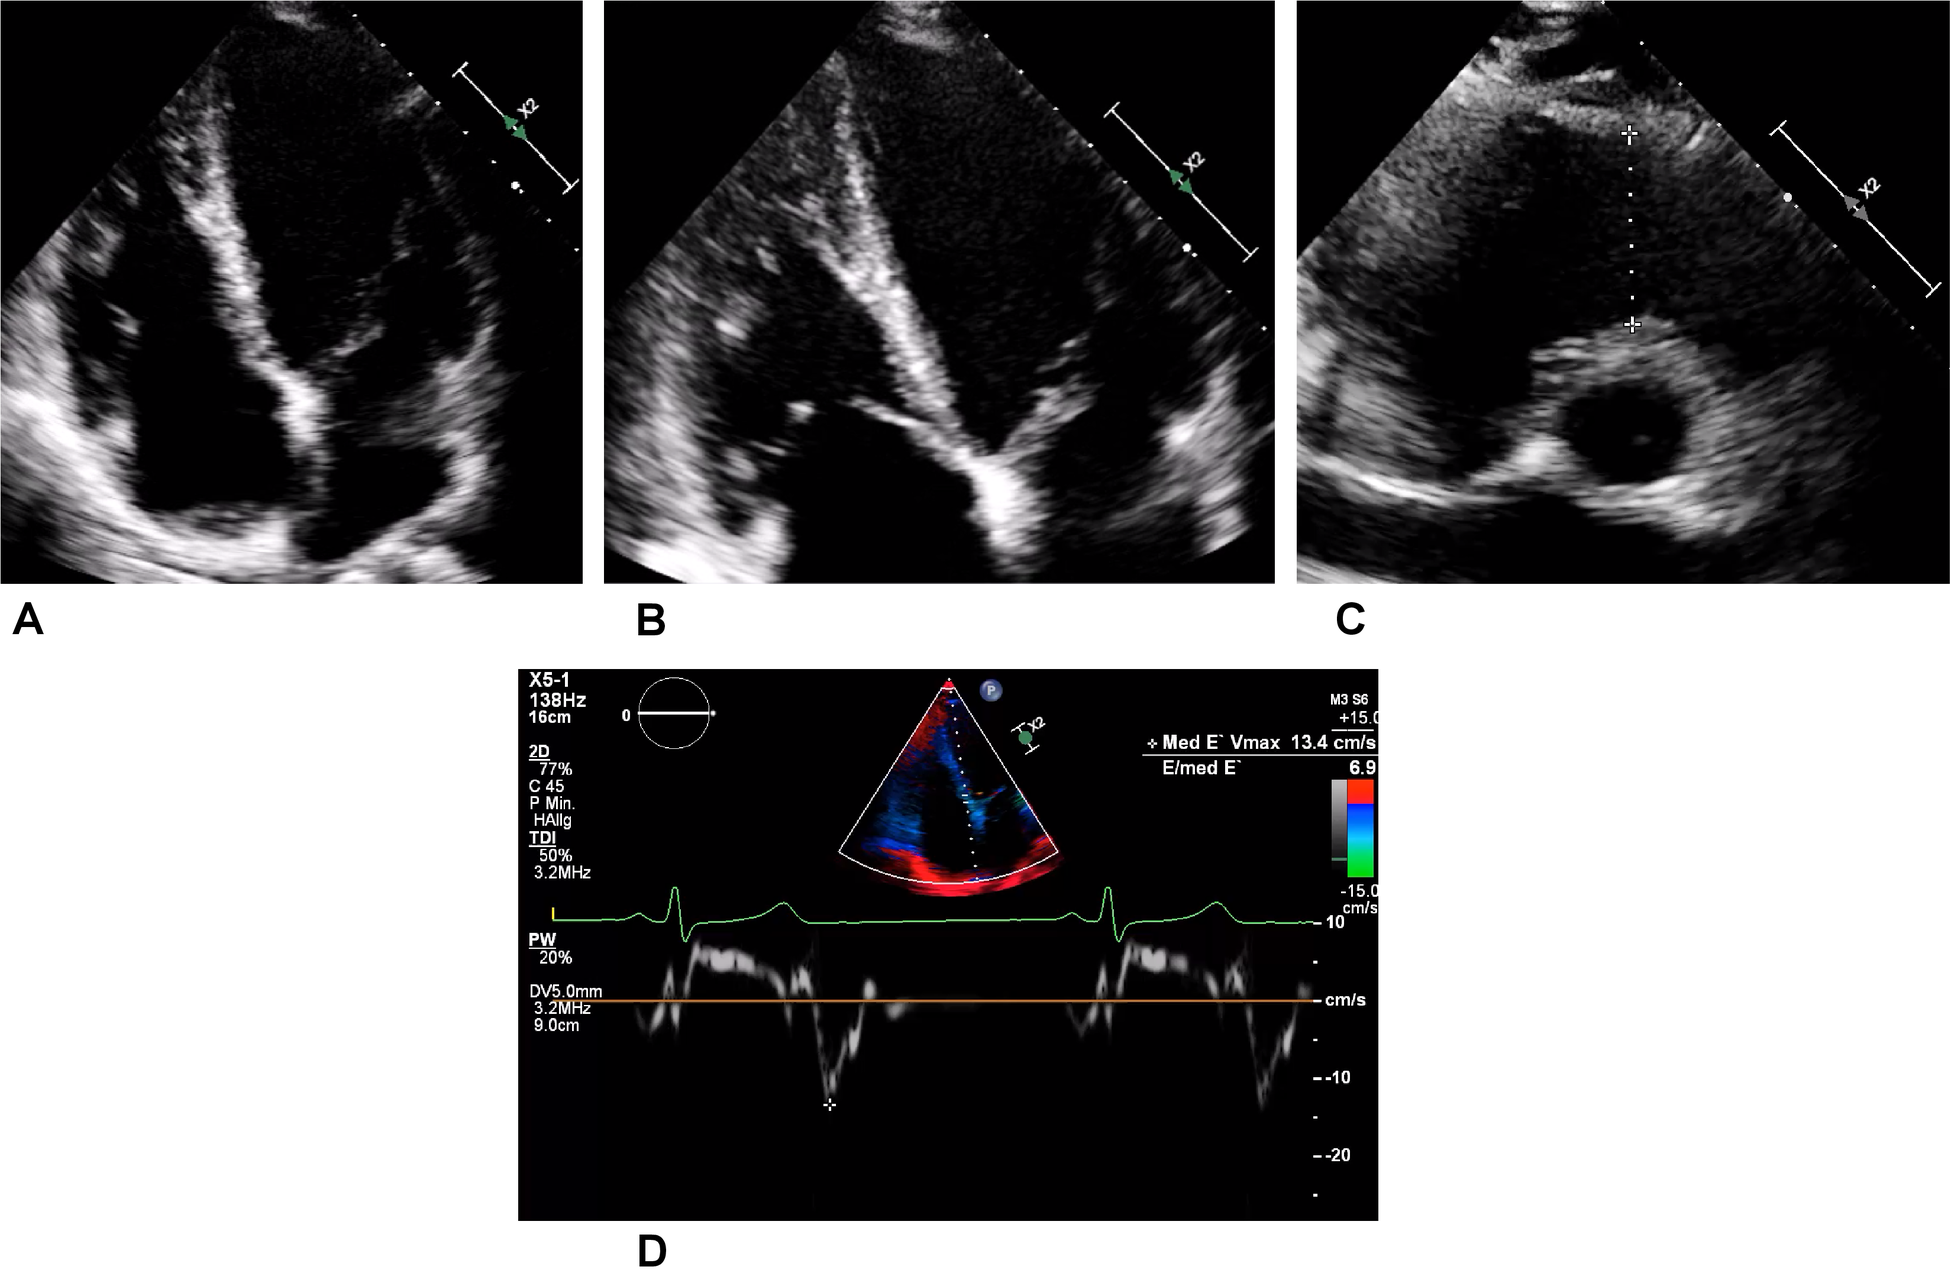

During this period, the athlete, who was still asymptomatic, took part in a training study in which troponin T levels were measured. These showed intermittent minor increases up to 30 ng/L (reference <14 ng/L) on non-exercising days. Notably, the athlete’s troponin I level was permanently within normal range, and the electrocardiogram (ECG) showed sinus rhythm without ST-segment alteration or T-wave inversions. Subsequent transthoracic echocardiography revealed a normal biventricular ejection fraction and diastolic function. Only the lateral aspect of the right ventricular (RV) free wall showed some hypertrabeculation, but the RV did not display apical aneurysms or hypokinesia (Figures 2A–D).

Figure 2. Transthoracic echocardiography of the asymptomatic athlete. (A) Regular four-chamber view. (B) Right dominant four-chamber view showing a trabeculated free wall in the right ventricle. (C) Slight dilatation of the right ventricular outflow tract (a distance of 34 mm is represented by the dotted line) in this normally sized young woman. (D) Medial tissue Doppler imaging revealing regular velocity.